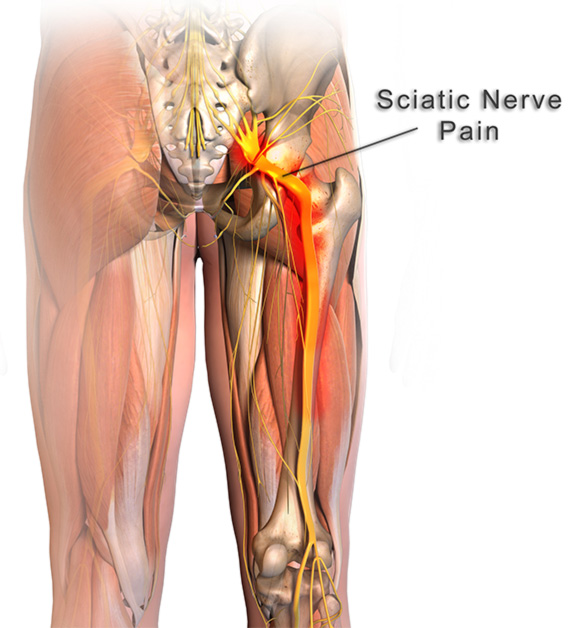

Download Sciatic nerve pain pictures